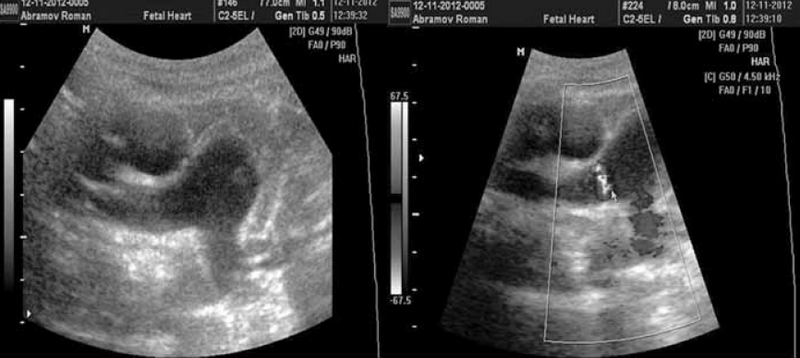

Диастолический сброс крови через коронарную фистулу в легочную артерию при постоянно-волновом допплеровском картировании отчасти напоминает аналогичный сброс через ОАП, однако является более низкоскоростным и менее продолжительным по времени, не занимая весь диастолический промежуток на допплерограмме (см. рис. 6).

Рис. 6. Диастолические потоки, отражающие сбросы крови через коронарную фистулу в ствол легочной артерии, визуализируются в секторе положительных значений над изолинией между систолическими и могут симулировать допплерограмму при классическом открытом артериальном протоке

В ходе работы был выявлен важный эхокардиографический диагностический признак. При ЭХО КГ сердца из левой парастернальной позиции по короткой оси на уровне ствола легочной артерии у 51 % детей с диагностированным ОАП имелся «дефицит» ткани аортолегочной связки (ligamentum arteriosum), визуализируемой в поперечном сечении непосредственно под бифуркацией ствола легочной артерии, а у 8 % детей ткань связки вовсе не визуализировалась (рис. 7).

Рис. 7. Визуализация аортолегочной связки (ligamentum arteriosum) в области бифуркации ствола легочной артерии (отмечено стрелкой). Дефицит или отсутствие ткани может указывать на наличие открытого артериального протока